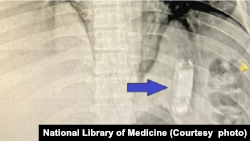

یک تیم از داکتران در شفاخانهٔ تشخیصیهٔ داخلهٔ دانشگاه منصورهٔ مصر یک تلیفون موبایل را از بطن یک زندانی بیرون کردند. این زندانی شش سال پیش تلیفون را بلعیده بود.

بر اساس گزارش رسانه‌های محلی، داکتران تلیفون موبایل را با استفاده از عمل اندیسکوپی، بدون جراحی، بیرون کشیدند. اما در مورد نوعیت تلیفون موبایل معلومات داده نشده است.

این زندانی که حبس ابداش را در زندان جمصه سپری می‌کرد به شفاخانه منتقل شد و داکتران با گرفتن ایکسری تلیفون را در معدهٔ وی یافتند.

داکتران به سرعت تشخیص دادند و تیم طبی فوراً دست به کار شده و عمل اندسکوپی را انجام داد. آنان توانستند در مدت ۴۵ دقیقه تلیفون را که در یک خریطهٔ پلاستیکی پیچانیده شده بود، از معدهٔ بیمار بیرون کنند.